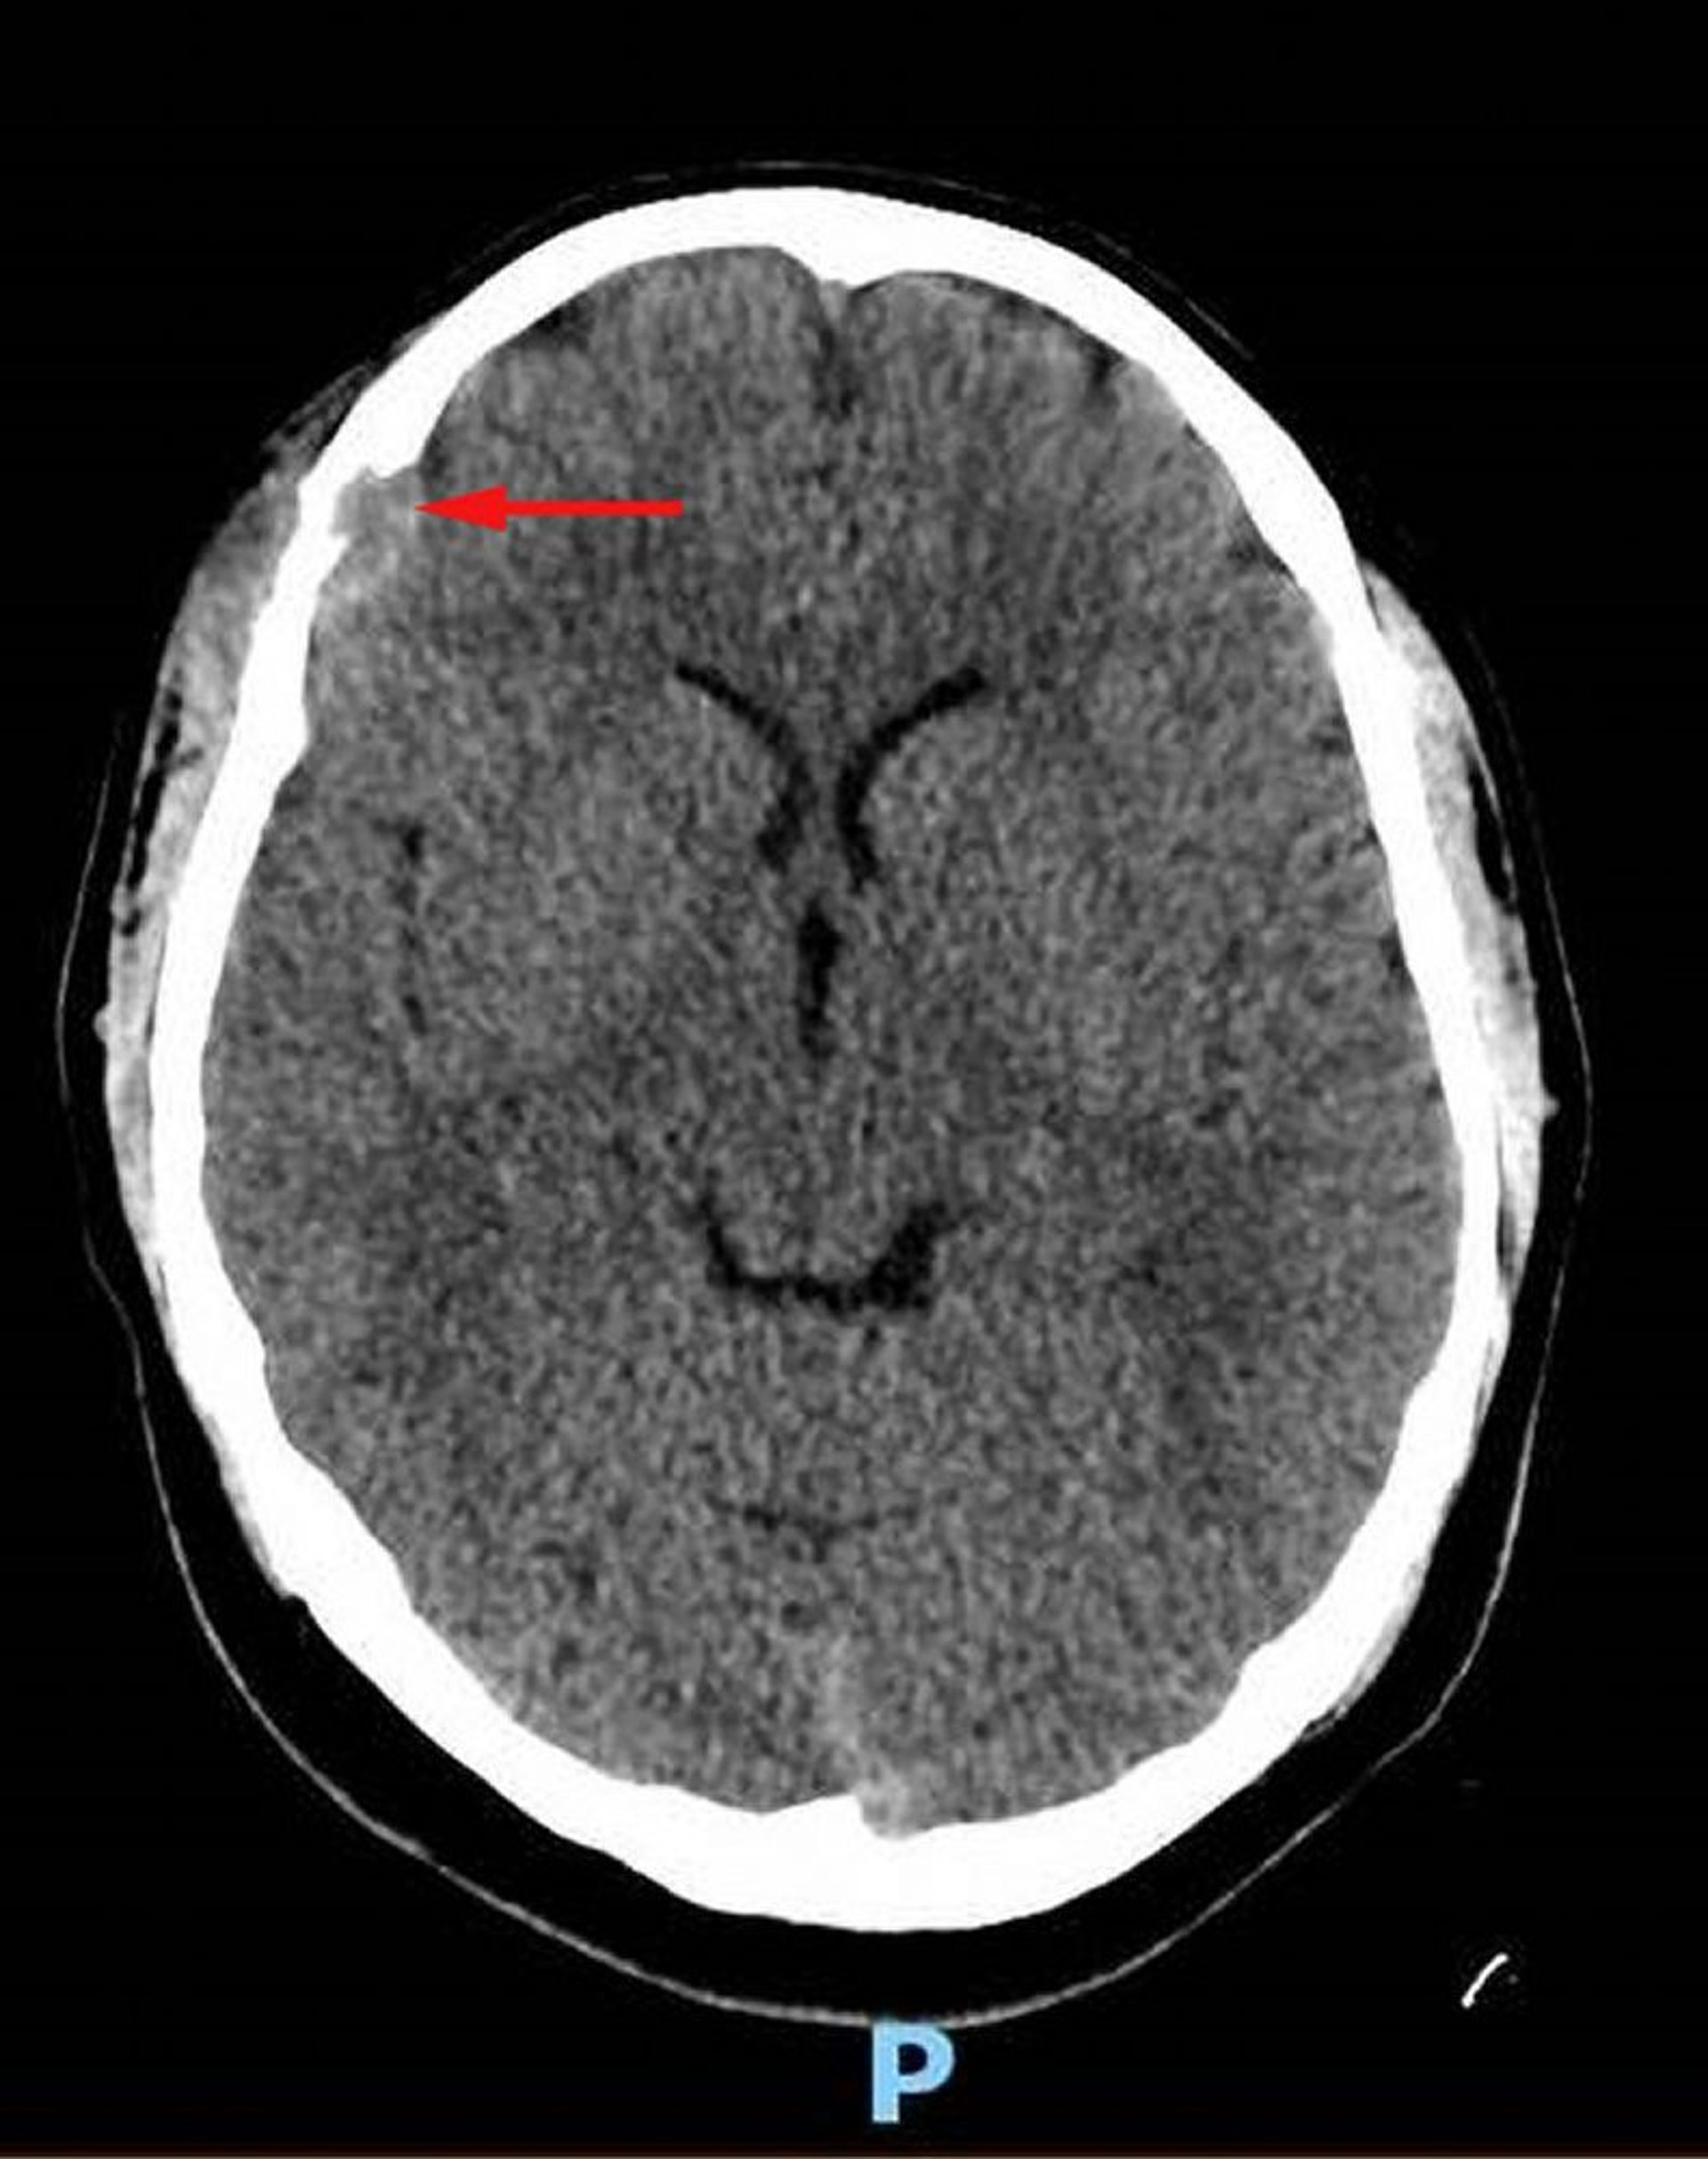

Лангергансоклеточный гистиоцитоз (КТ головы)

На этом снимке показано поражение мягких тканей в правой лобной кости с сопутствующим разрушением костной ткани и внутричерепным распространением мягких тканей в дуральное пространство (красная стрелка). Имеется асимметричное расположение мягких тканей кожи головы. Биопсия была диагностической для клеточного гистиоцитоза Лангерганса.

Image courtesy of Carolyn Fein Levy, MD, and Jeffrey M. Lipton, MD, PhD.